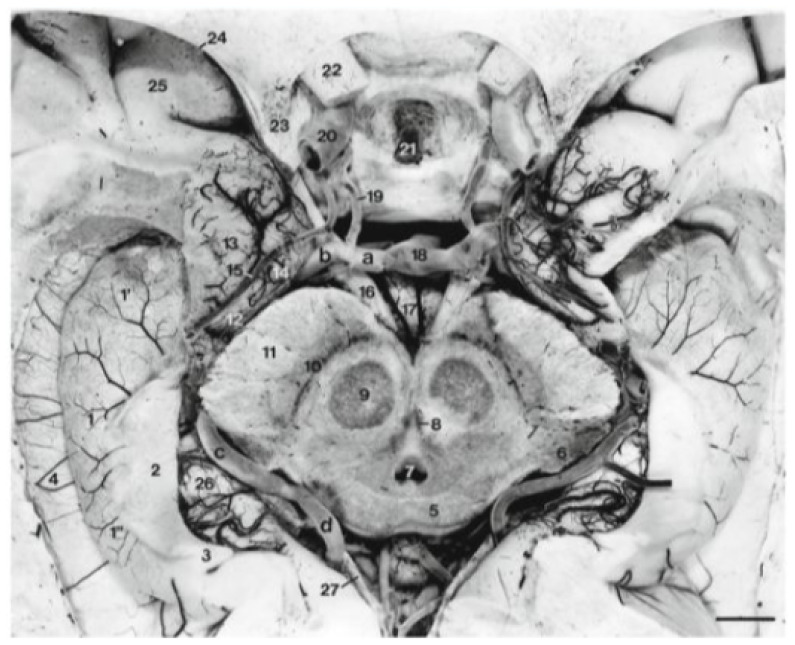

Delineating Neuroanatomical Structures for the Measurement of Temporal Horn Dilatation.